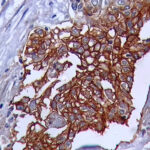

IHC on Tongue Squamopus Cell Carcinoma TissueAnti-GLUT 1